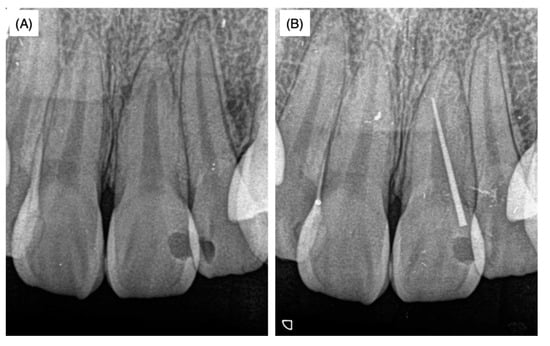

A female patient aged 18 years was referred to a private dental clinic for cosmetic problems caused by a black-colored left maxillary central incisor. As swelling in the attached gingiva surrounding the upper left maxillary incisor was observed, X-ray analysis was performed with and without the insertion of gutta-percha points (GC Dental Industrial Corp, Tokyo, Japan) in the sinus tract in order to identify the lesion area (Figure 1A,B).

As there was no response to the electric pulp test in the affected tooth, the pulpal cavity was accessed and standard endodontic treatments including reaming, filing, root irrigation and application of a Ca(OH)2 water-based paste (Calcipex II®, Nippon Shika Yakuhin Co., Ltd., Yamaguchi, Japan) were conducted three times. The patient was then introduced to Hiroshima University Hospital and the above details and dental radiographs (Figure 1A,B) were provided in the response letter from the dentist at the private clinic to our inquiry. According to the history-taking at the university hospital, when the patient was around 10 years old, the tooth developed severe caries and was restored using composite resin at another private dental clinic. As the patient did not remember the name and address of the dental clinic where this initial treatment was performed, no further information on the initial treatment was available.

Slight pressure pain and notable fistulization were identified in the swollen area. However, no spontaneous pain or significant perpendicular or horizontal percussion pain was identified. The probing depth of the left maxillary incisor was within 2 mm and tooth movement was within physiological limits; thus, root fracture was not assumed. The palatal side was sealed with hydraulic cement. Dental radiographs taken at the first visit to the university hospital as well as radiographs provided by the private dental clinic revealed that the width of the root canal adjacent to the apex of the left maxillary incisor was narrower than that of the maxillary right central incisor (Figure 1 and Figure 2B). The upper two-thirds of the crown side were filled with Calcipex II® from the previous treatment. Moreover, the width of the periodontal ligament space was slightly enlarged (Figure 1 and Figure 2B).

Figure 1. X-ray films without (A) and with (B) the insertion of gutta-percha points when the patient was 18 years and 8 months old. These X-rays were taken at a private dental clinic before the patient came to our university dental hospital.